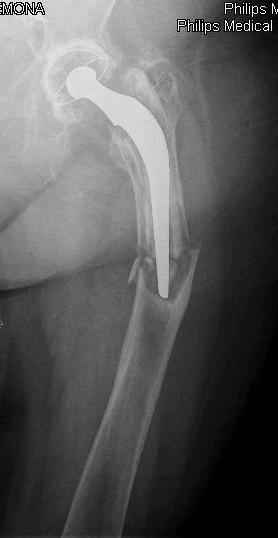

I generally should prefer a long stem revision prosthesis, as that allegated.

rs> I generally should prefer a long stem revision prosthesis, as that allegated.